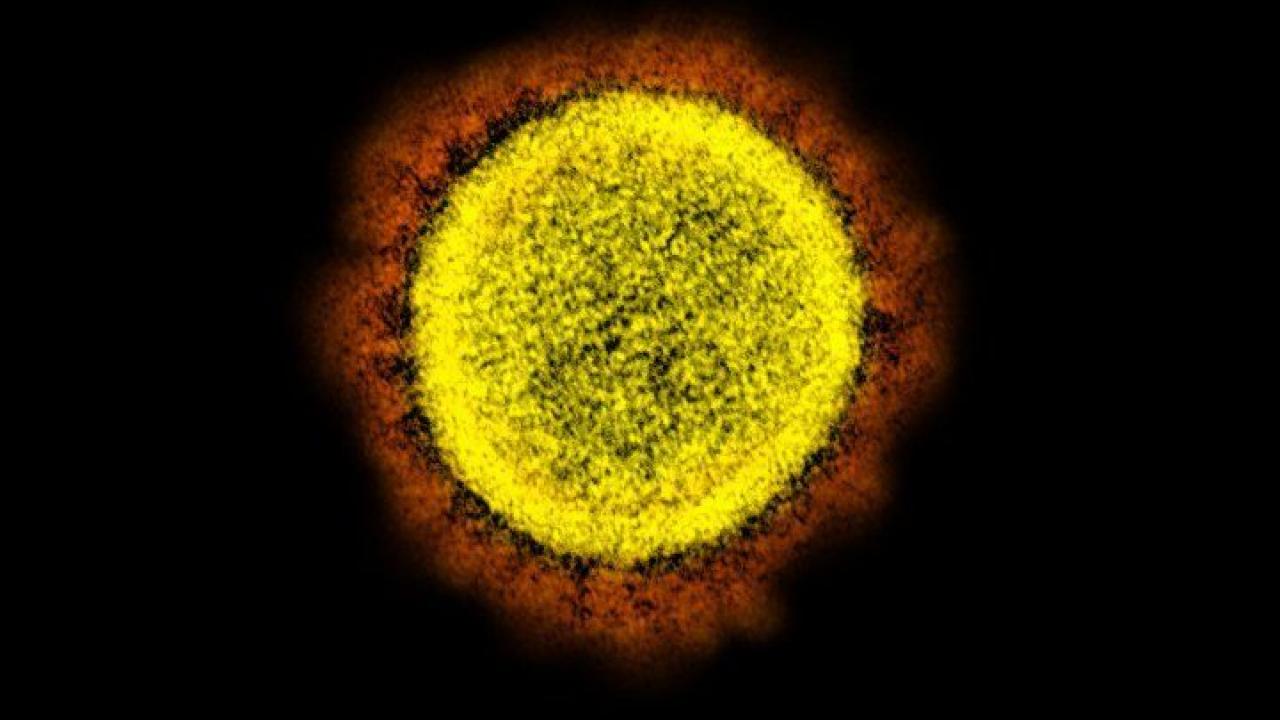

Transmission electron micrograph of the SARS-CoV-2 virus. Image credit: NIAID